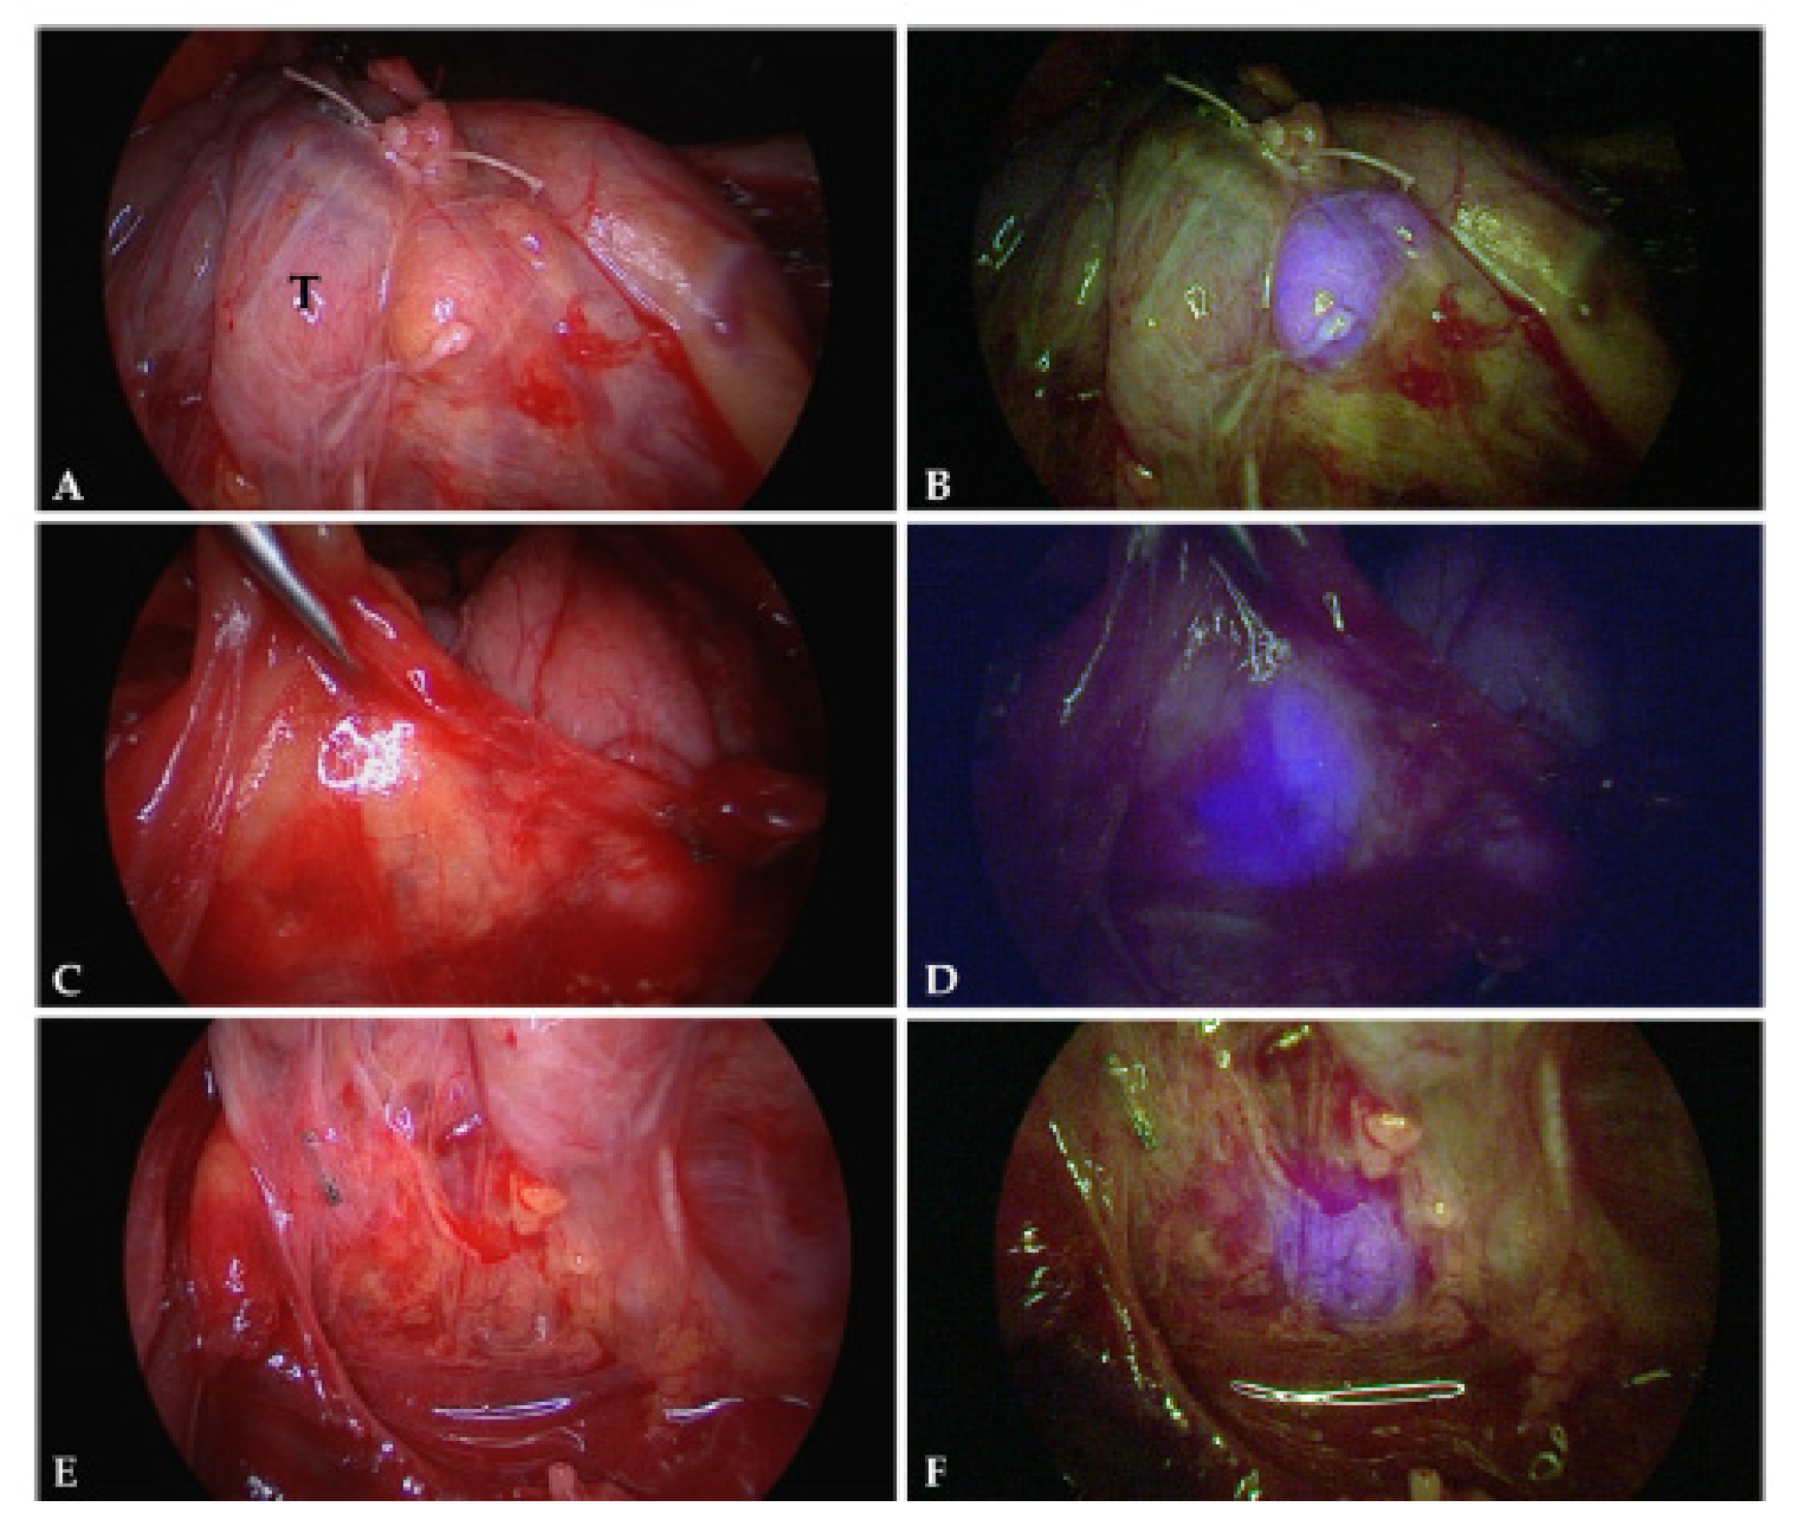

- Wizenty, J.; Schumann, T.; Theil, D.; Stockmann, M.; Pratschke, J.; Tacke, F.; Aigner, F.; Wuensch, T. Recent Advances and the Potential for Clinical Use of Autofluorescence Detection of Extra-Ophthalmic Tissues. Molecules 2020, 25, 2095. [Google Scholar] [CrossRef]

- Langhout, G.C.; Spliethoff, J.W.; Schmitz, S.J.; Aalbers, A.G.J.; van Velthuysen, M.L.F.; Hendriks, B.H.W.; Ruers, T.J.M.; Kuhlmann, K.F.D. Differentiation of Healthy and Malignant Tissue in Colon Cancer Patients Using Optical Spectroscopy: A Tool for Image-Guided Surgery. Lasers Surg. Med. 2015, 47, 559–565. [Google Scholar] [CrossRef]

- Lauwerends, L.J.; Galema, H.A.; Hardillo, J.A.U.; Sewnaik, A.; Monserez, D.; van Driel, P.B.A.A.; Verhoef, C.; Baatenburg de Jong, R.J.; Hilling, D.E.; Keereweer, S. Current Intraoperative Imaging Techniques to Improve Surgical Resection of Laryngeal Cancer: A Systematic Review. Cancers 2021, 13, 1895. [Google Scholar] [CrossRef] [PubMed]

- Osman, H.; Georges, J.; Elsahy, D.; Hattab, E.M.; Yocom, S.; Cohen-Gadol, A.A. In Vivo Microscopy in Neurosurgical Oncology. World Neurosurg. 2018, 115, 110–127. [Google Scholar] [CrossRef] [PubMed]

- Wang, M.; Long, F.; Tang, F.; Jing, Y.; Wang, X.; Yao, L.; Ma, J.; Fei, Y.; Chen, L.; Wang, G.; et al. Autofluorescence Imaging and Spectroscopy of Human Lung Cancer. Appl. Sci. 2017, 7, 32. [Google Scholar] [CrossRef]

- Sun, S.; Yang, Y.; Chen, M.; Wang, L.; Pan, H.; Zhang, X.; Wagnieres, G.; Mohammad, Y.; Barreiro, E.; Pirozzolo, G.; et al. Comparison of Autofluorescence and White-Light Bronchoscopies Performed with the Evis Lucera Spectrum for the Detection of Bronchial Cancers: A Meta-Analysis. Transl. Lung Cancer Res. 2020, 9, 23–32. [Google Scholar] [CrossRef] [PubMed]